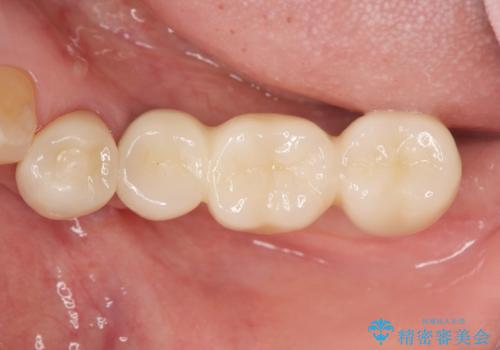

チタンカスタムアバットメントを用いた清掃性の高いインプラント治療

清掃のしやすさと審美性・強度に優れるチタン製カスタムアバットメントとジルコニアクラウンによる補綴治療を計画します。

インプラント治療を行ったことでしっかりと噛めるようになり、また清掃性の高い環境を整備したことで長期的な予後も期待することができます。